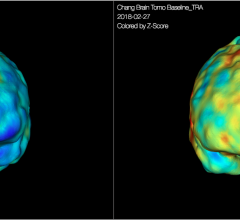

March 15, 2018 – CereMetrix, a subsidiary of CereHealth Corp., has received 510(k) clearance from the U.S. Food and Drug ...